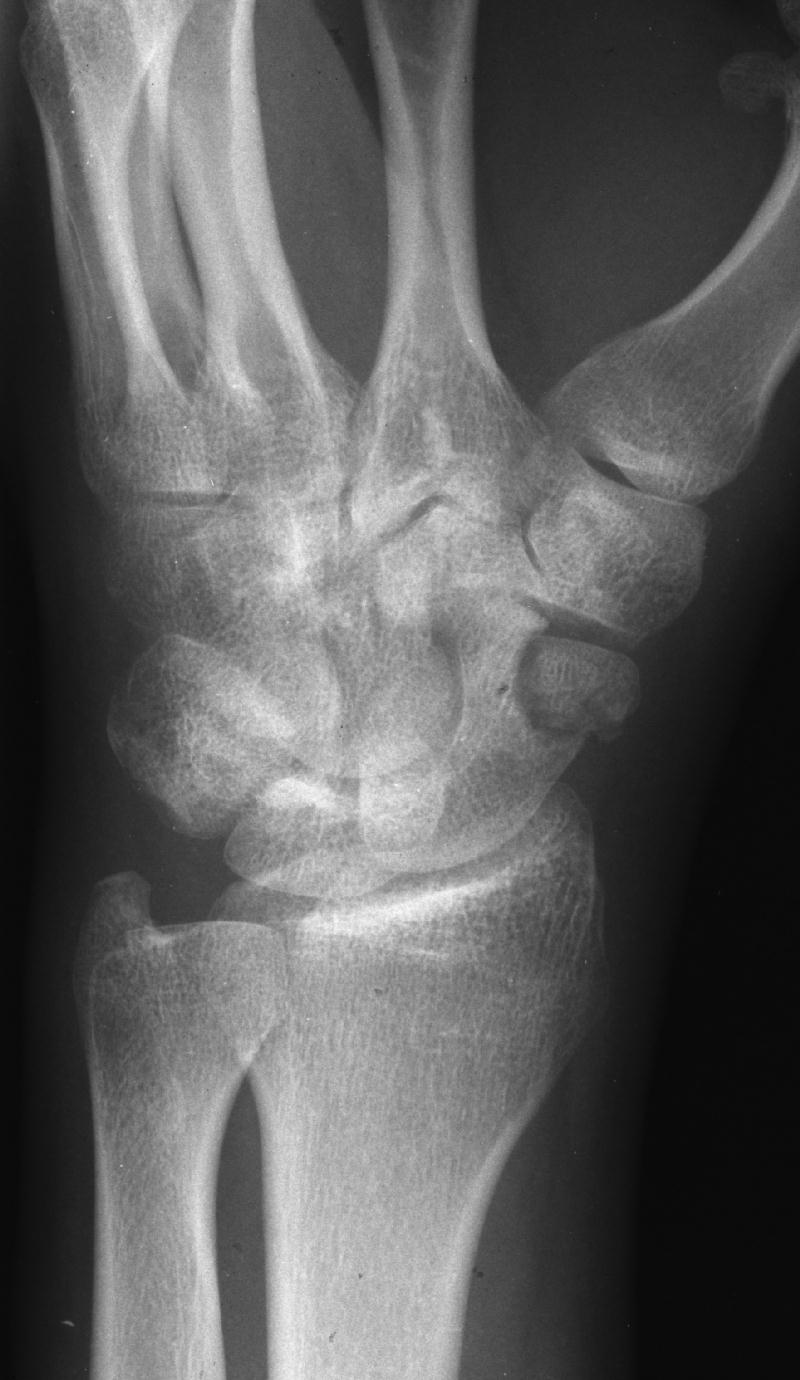

Clinical Example: Scaphoid Tubercle Fracture

scaphoid tubercle fracture